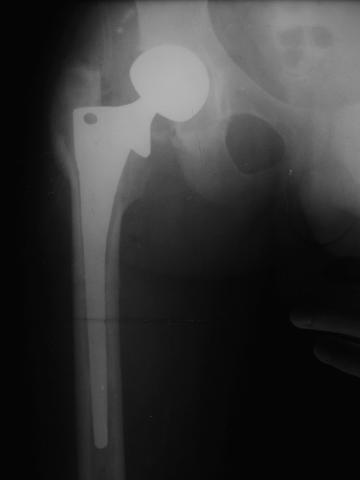

Лечился в стержневом аппарате по месту жительства. АВФ демонтировали через полгода из-за воспаления в области стержней (рис 2). После демонтажа в течение месяца больной лихорадил до 38*, были боли в бедре. Эти явления исчезли после курса антибиотиков. Через год после травмы в ЦРБ ему имплантировали биполярный протез (рис 3). Рана зажила первично. Ходил с костылями, слегка приступая на ногу. На контрольных осмотрах выявлена прогрессирующая протрузия (рис 4-6).

Планируем через малый разрез взять образцы тканей для тщательного бакисследования. При отсутствии инфекции - поставим антипротрузионное кольцо Мюллера с цементной чашкой и костной пластикой из гребня подвздошной кости. В противном случае - выкинем все железо.

Если нет явных признаков воспаления (клинических и лабораторных) то я бы предпринял одноэтапную ревизию с заменой обоих компонентов сутава. Кольцо

Мюллера не есть антипротрузионное - это моделирующее кольцо и вряд ли здесь подойдет. В данном случае - кольцо Бурша -Шнайдера или Ганса более логичны, так как они истино антипротрузионные. Огромный дефект следует закрыть костью на будущие ревизии. При инфекции - шанс на двухэтапную ревизию есть, но риски значительные. риски выбирает пациент. В любом случае - это следует делать умелыми руками при хорошем материальном обеспечении. А Рыков.

Стоит ли менять сейчас бедренный компонент? Пока явных признаков нестабильности его не видно.

Да, согласен полностью. Burch-Schneider понадежнее будет.